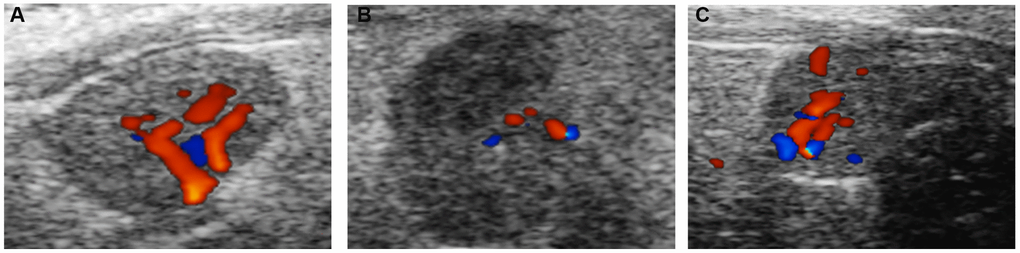

The ovarian area of the mice in the aging non-intervention group was smaller than that in the normal group (P = 0.0076), and the ovarian area in the aging intervention group was larger than that in the non-intervention group (P = 0.0210) (Figure 2, Table 1). The ovarian blood flow in the normal group was rich, the mice in the aging non-intervention group were weak or even disappeared, and the blood flow in the intervention group was richer than that in the non-intervention group (Figure 3). Pulse pressure, pulse index and resistance index were higher in aging non-intervention group than in normal group. After drug administration intervention, pulse pressure and pulse index decreased (Table 2).

Figure 3. Ovarian blood flow under ultrasound. (A) Normal group; (B) Natural aging non-intervention group; (C) Natural aging intervention group.